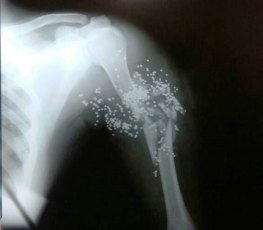

Os dois criminosos roubaram um aparelho celular, um cordão de ouro e mesmo sem a vítima reagir um deles atirou